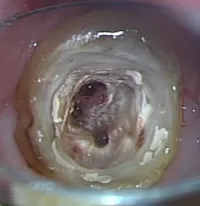

[使用例①]歯根の治療

![[使用例①]歯根の治療](/wp-content/uploads/unnamed-10.png.webp)

歯根の細菌や汚れを除去する際、従来は手先の感覚や歯の削りカスを見て判断するなど、経験とカンに頼る部分が多くありました。

マイクロスコープを用いることで、根の中の状態を目でしっかり確認できるようになり、より確かな細菌や汚れの除去ができるようになりました。

当院ではマイクロススコープを3台装備しております。